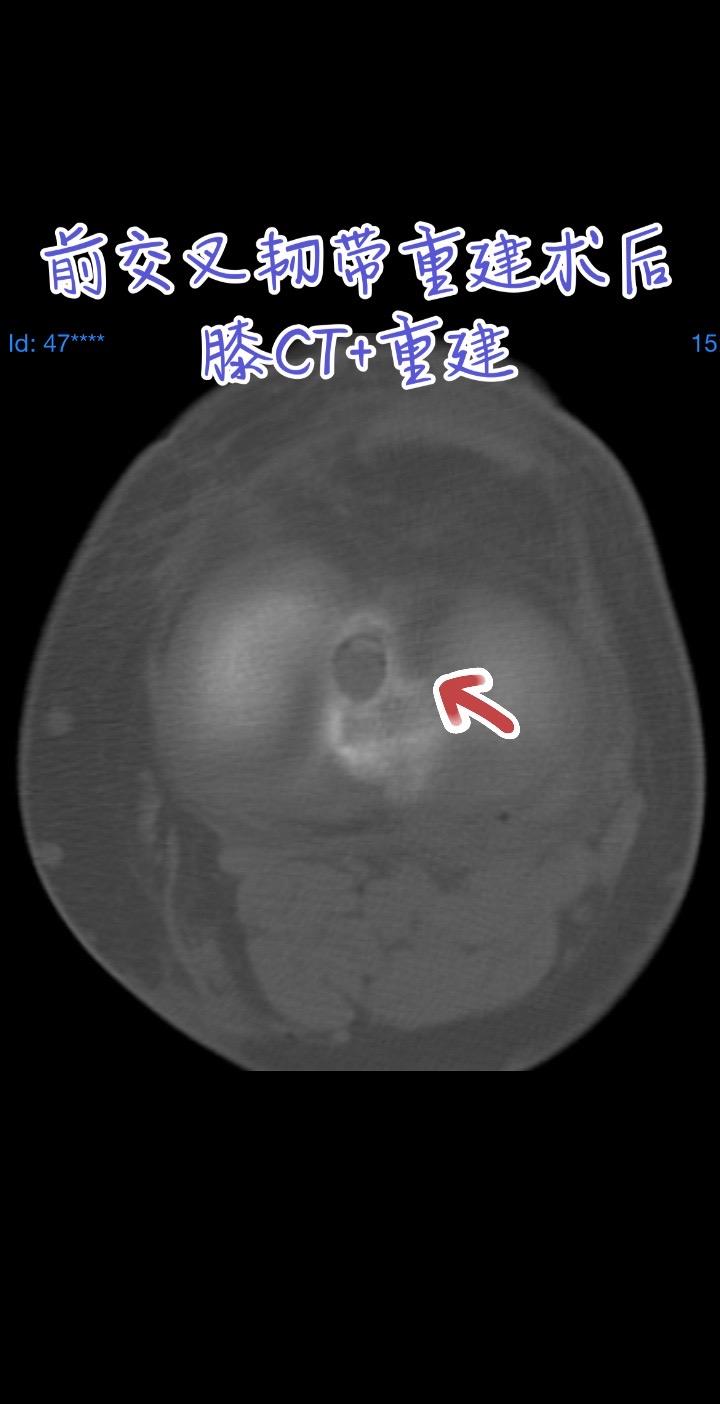

前交叉韧带重建。每一张图片,都是对细节的苛求;每一次重建,都是对精准的不懈探索。